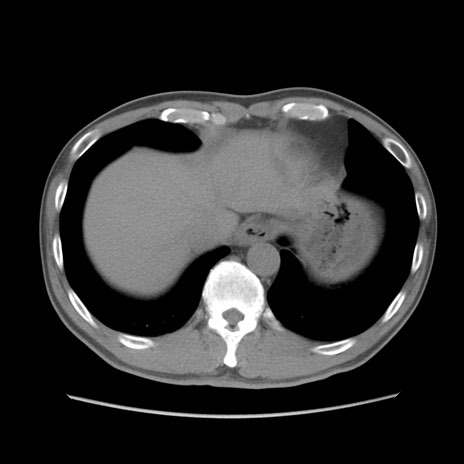

症例56 CT(横断像)

脂肪ウインドウ